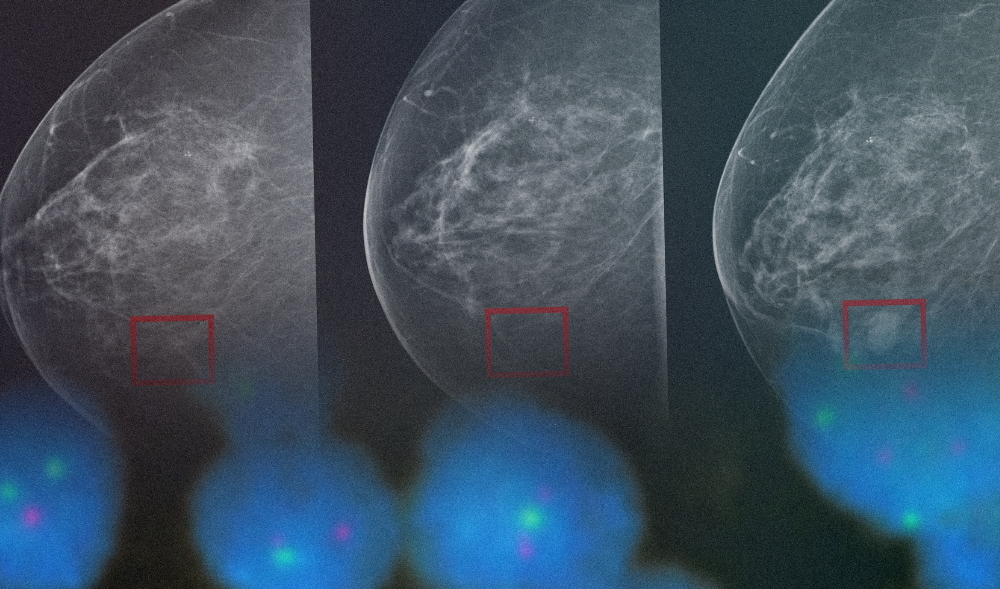

Estos mecanismos pueden cambiar a lo largo del tiempo, activando o inactivando genes sin necesariamente cambiar la composición genética de nuestro ADN. Como la naturaleza de la epigenética es dinámica y reversible, juega un rol vital en el desarrollo temprano del cáncer y algunos tratamientos se enfocan en estudiar las ventajas de estos eventos (Imagen 1).

Imagen 1. Regulación Epigenética en cáncer. Las alteraciones Epigenética en el cáncer regulan diversas respuestas celulares, incluyendo la proliferación, apoptosis, invasión y senescencia. Esto se regula a través de la metilación del ADN, la modificación de histonas, la remodelación de la cromatina y la regulación de ARN no codificante evidenciando que la Epigenética juega un rol importante en la génesis de un tumor cancerígeno.